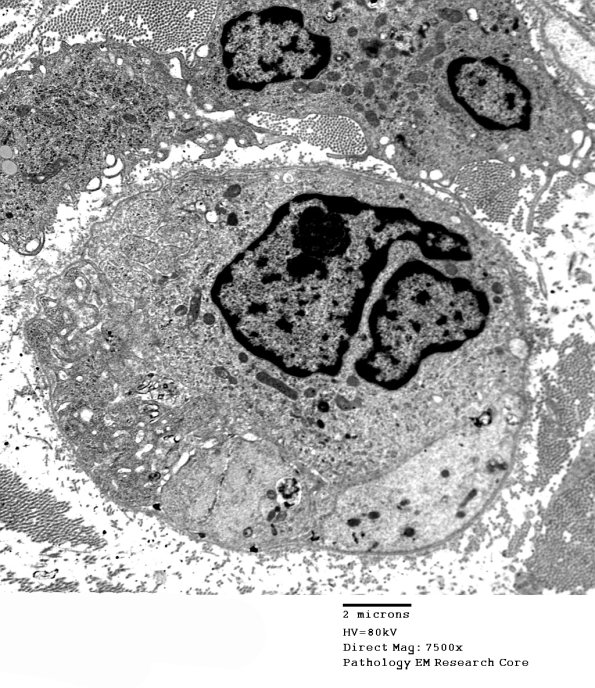

2F2A,B A demyelinated axon with an intra-Schwann cell adjacent macrophage with numerous pseudopods. Notice the adjacent endoneurial macrophage. (electron micrograph)